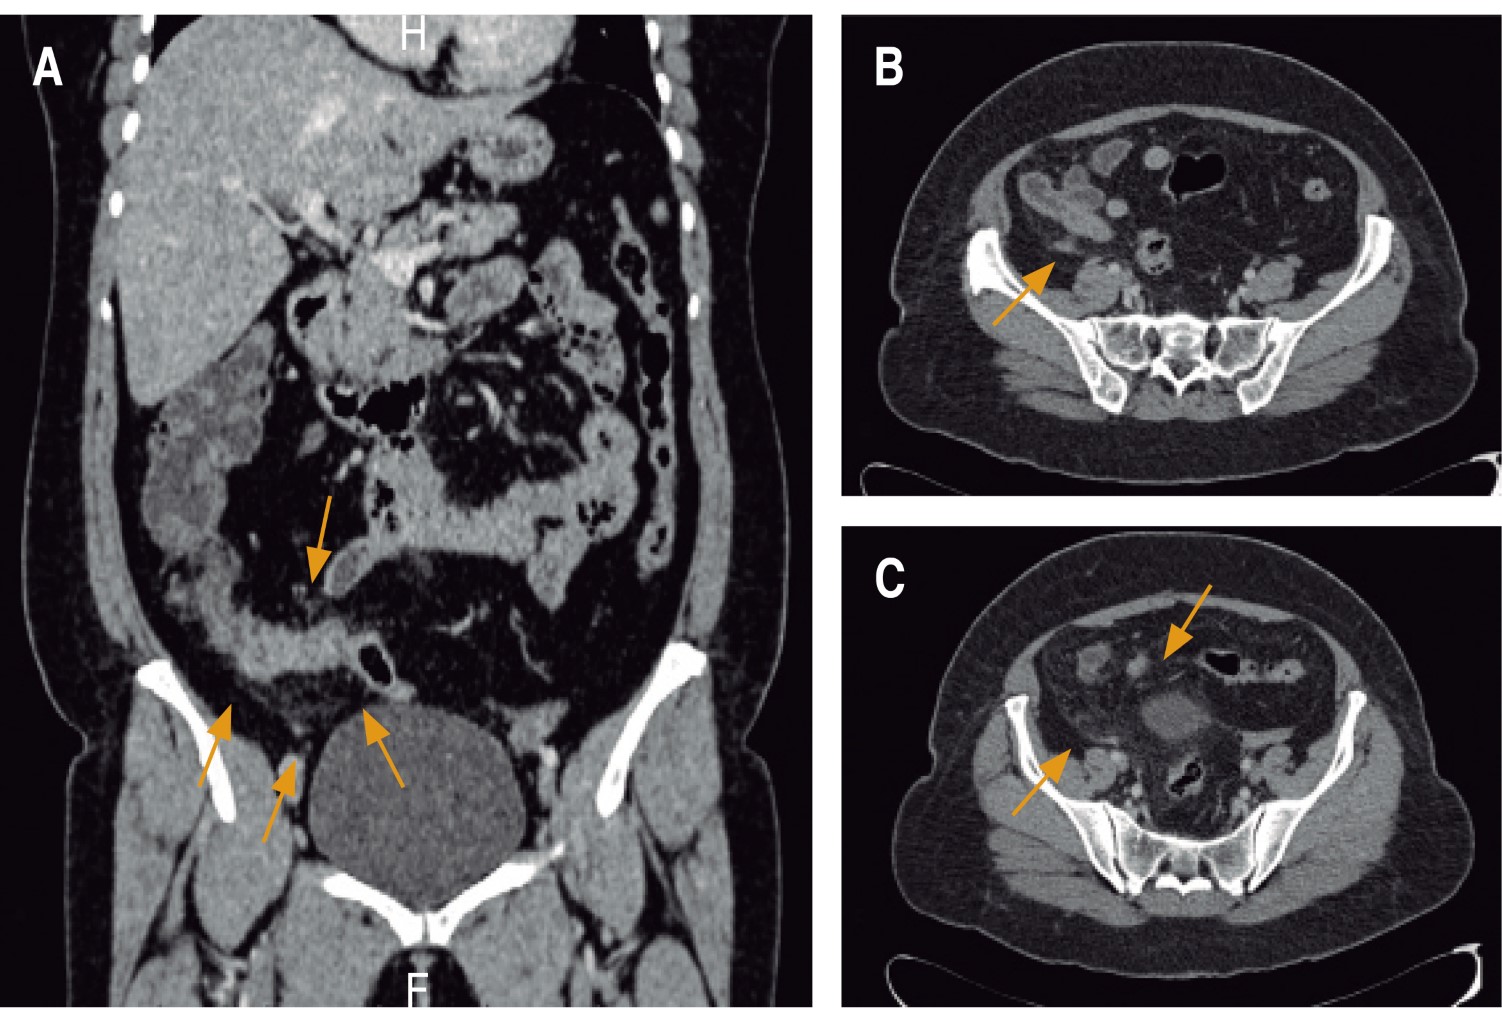

Physical examination revealed abdominal pain on deep palpation in the right iliac fossa with positive McBurney's point, and obturator, psoas, and Von Blumberg's signs. She also had positive right upper and middle ureteral points and right Giordano sign. Complete laboratory tests, including blood cytology, blood chemistry, and acute phase reactants were requested. The only important findings were leukocytosis with neutrophilia of 94% and C-reactive protein of 4.3 mg/dl. An abdominal CT scan with intravenous contrast was performed (Figure 1) that showed inflammatory changes of peri-colonic fat on the right side, and no identification of the cecal appendix.

Figure 1